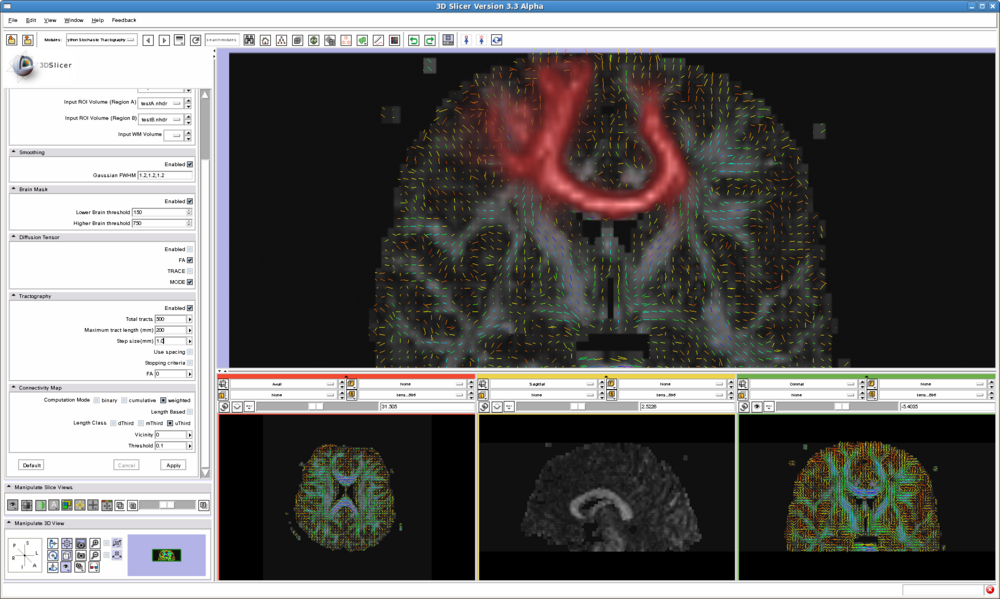

| − | |[[Image: | + | |[[Image:General.png|thumb|1000px|Stochastic tractography panel]] |

Quick Tour of Features and Use

List all the panels in your interface, their features, what they mean, and how to use them. For instance:

- IO panel:

- Smoothing panel:

- Brain Mask panel:

- Diffusion Tensor panel:

- Tractography panel:

- Connectivity Map panel: